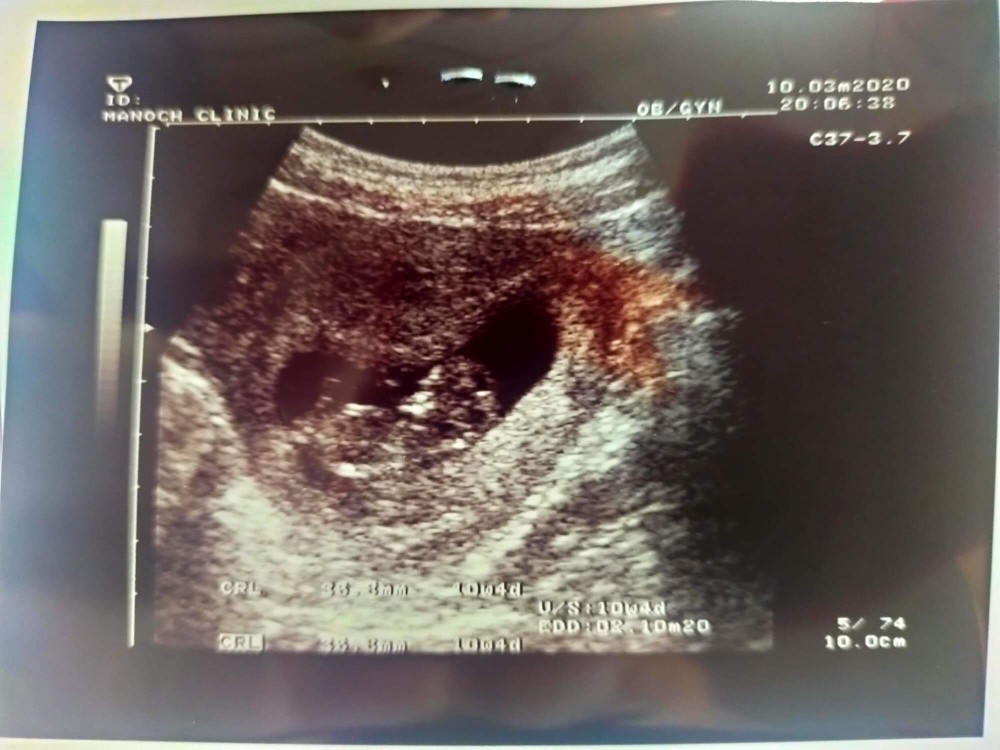

ของเราตอน10w+3

10weekจ้า